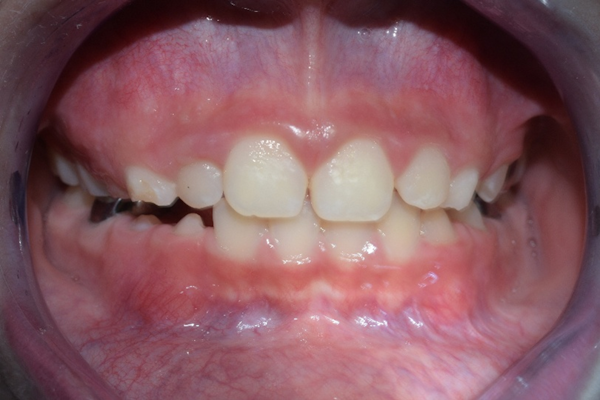

El paciente feliz, al finalizar su tratamiento

Cuando no se corrige a tiempo, este tipo de problema puede provocar:

- Mayor grado de apiñamiento en la adolescencia

- Tratamientos más largos y complejos

- Problemas en la mordida y función

- Riesgo aumentado de caries y enfermedad periodontal